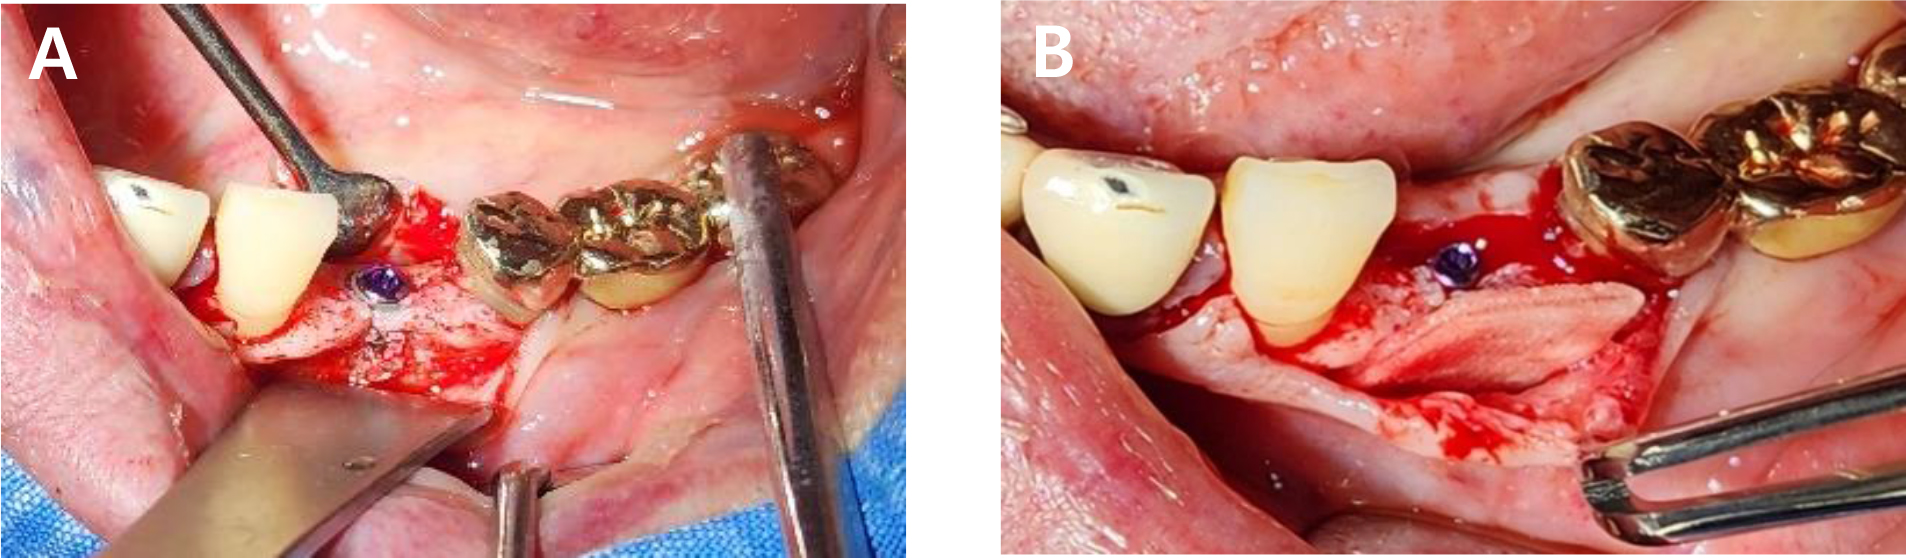

- Alveolar Ridge Preservation via Intrasocket Granulation Tissue Repositioning: Technical Note on a Novel Flap Design

- Byoung-Kyou Park, Won-Pyo Lee

- This case report presents a novel, biologically driven approach for alveolar ridge preservation (ARP) using intrasocket granulation tissue repositioning in conjunction with …

- This case report presents a novel, biologically driven approach for alveolar ridge preservation (ARP) using intrasocket granulation tissue repositioning in conjunction with a Bone-Key (BK) incision. A 42-year-old female patient with severe bone loss around tooth #11 underwent ARP using an intrasocket granulation tissue repositioning protocol. The intrasocket granulation tissue was preserved and coronally repositioned to function as a biological sealing layer, whereas the BK incision enabled tension-free flap advancement without compromising the mucogingival junction. No barrier membrane or additional soft tissue grafting was required as a socket-sealing material. Favorable soft tissue healing and ridge volume stability were observed after 2 months, followed by successful implant placement. Radiographic and clinical evaluations at 18 months confirmed stable marginal bone levels and healthy peri-implant soft tissue. This case suggests that the intrasocket granulation tissue repositioning protocol may be a valuable, minimally invasive strategy for ridge preservation, particularly in periodontally compromised sites. Further studies are needed to validate long-term outcomes and define indications for the selective preservation of intrasocket granulation tissue. - COLLAPSE